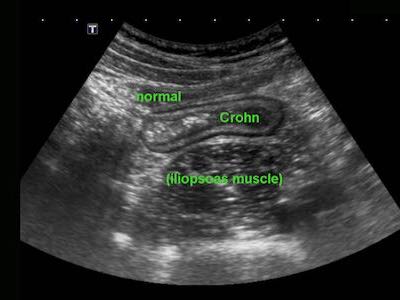

Đo độ dày thành ruột được thực hiện tốt nhất và có tính tái lập cao nhất trong khi ép, như ở đây trên một người bình thường (bên trái) và ở một bệnh nhân mắc bệnh Crohn (bên phải).

Các phép đo được thực hiện từ bờ ngoài của lớp cơ đến phía đối diện, sau đó chia cho 2, cho kết quả độ dày thành lần lượt là 1,5 mm và 6,5 mm đối với hồi tràng bình thường và hồi tràng Crohn.

Ở những bệnh nhân có bệnh Crohn hoạt động rõ ràng, cấu trúc siêu âm bình thường của thành ruột có thể bị mất lan tỏa.

Lưu ý mô mỡ tăng âm (fat) xung quanh hồi tràng, đại diện cho mạc treo và mạc nối đang viêm, đang cố gắng bao bọc lại vị trí thủng sắp xảy ra.

Trong những trường hợp như thế này, hình thái thay đổi và lòng ruột hẹp lại có thể bắt chước hình ảnh ác tính.